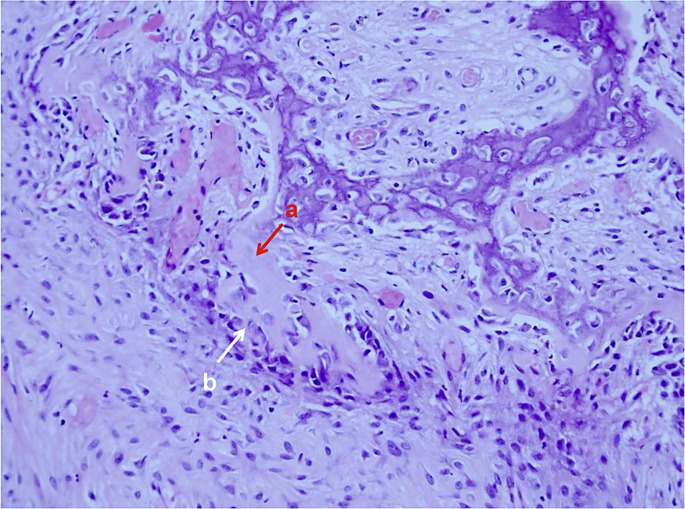

Introduction: Mucoceles are benign, slow-growing cystic formations located within the paranasal sinuses, caused by complete ostial obstruction and accumulation of mucous secretions. Here, we report a case of a patient who initially presented with unilateral painless visual impairment and was ultimately diagnosed with bilateral sphenoid sinus mucoceles (SSMs) after two hospitalizations.

Case presentation: A 67-year-old woman presented with a 7-day history of decreased vision in her left eye. She denied any orbital pain, headache, or restricted eye movement and was diagnosed with retrobulbar ischemic optic neuropathy on the first admission. After drug treatment, the visual acuity of patient improved significantly, but 3 months after discharge, the patient was hospitalized again due to recurrent vision loss accompanied by left orbital pain and left temporal pulsatile headaches. After multiple imaging examinations, the patient was ultimately diagnosed with SSMs and her visual acuity was restored after surgical treatment.